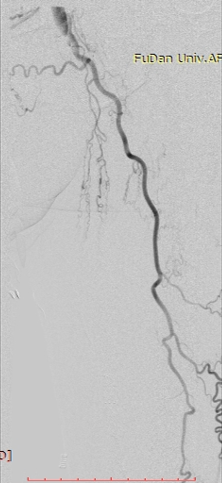

病例-1 男性,77岁,左下肢SFA支架术后7年,旁路术后3年静息痛 ABI:左侧 0.35